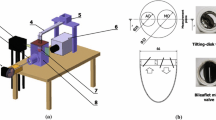

The Isolated Heart

Hearts of 4 landrace pigs (80–106 kg) were explanted according to the protocol described previously.22 Briefly, a median sternotomy was performed in the anesthetized pigs and the aorta was cannulated with a cardioplegic needle. After exsanguinating around 2 L of blood via the iliac artery, the ascending aorta was clamped distally to the cardioplegic needle and 1 L of Custodiol (Dr. Franz Köhler Chemie GmbH, Bensheim, Germany) was slowly applied. Simultaneously, the heart was cooled with a slurry ice solution. The heart was then excised and prepared for the connection to the isolated heart apparatus. All vessels of the right atrium were ligated using 4-0 Prolene sutures. All vessels of the left atrium were also closed except one pulmonary vein that was connected to the preload reservoir. The HVAD (Medtronic plc, Dublin, Ireland) sewing ring was attached to the ventricular apex to facilitate coring and pump implantation with orientation of the LVAD inflow cannula towards the mitral valve.

The isolated heart apparatus featured three connections to the heart: First, the aorta was connected to an air-trapped reservoir mimicking the arterial Windkessel53 system; Second, the pulmonary artery was connected to an open venous reservoir to eject the coronary flow against a low pressure; Third, the left atrium was cannulated and connected to a pressure-controlled air-trapped reservoir which constituted the preload adjustment system (Fig. 1).

For cardiac resuscitation, Langendorff perfusion was used as the pressure in the arterial reservoir was gradually increased until 70 mmHg was reached.22 Thereby, the coronary arteries were perfused with oxygenated blood and the heart was rewarmed to a normothermic temperature of 37 °C. If necessary, the hearts were defibrillated and/or paced to achieve a stable sinus rhythm. Once the heart stabilized, an HVAD was attached and the setup was switched to the working mode, in which the heart pumps blood from the preload reservoir towards the arterial one. By adjusting the preload, afterload, and pump speed, different levels of LVAD support (unsupported, full, and partial support) were achieved. Characteristic pressure (APT300, Harvard Apparatus, Hollisten, MA, USA, see Fig. 1) and flow signals (SONOFLOW CO.55/120, Sonotec, Halle, Germany, see Fig. 1) were recorded with a signal processing and control board (MicroLabBox, dSPACE GmbH, Paderborn, Germany).